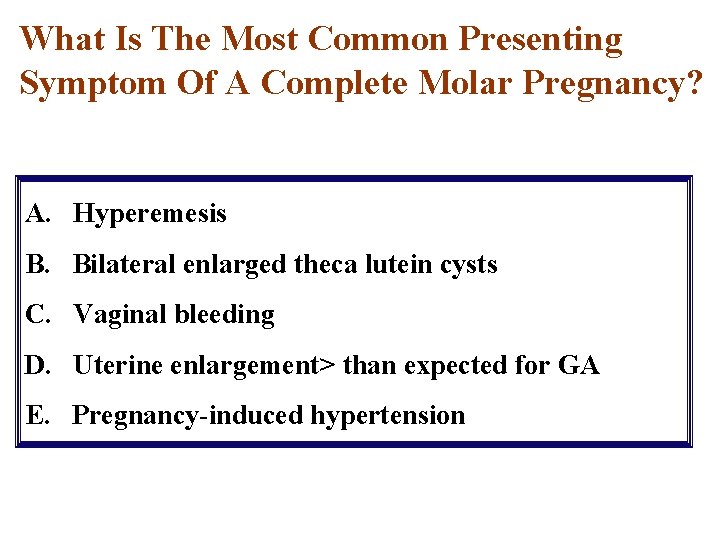

What Is The Most Common Presenting Symptom Of A Complete Molar Pregnancy? A. Hyperemesis B. Bilateral enlarged theca lutein cysts C. Vaginal bleeding D. Uterine enlargement> than expected for GA E. Pregnancy-induced hypertension

What Is The Most Common Presenting Symptom Of A Complete Molar Pregnancy? A. Hyperemesis 10% B. Bilateral enlarged theca lutein cysts 30% C. Vaginal bleeding 85% D. Uterine enlargement> than expected for GA 40% E. Pregnancy-induced hypertension 1%